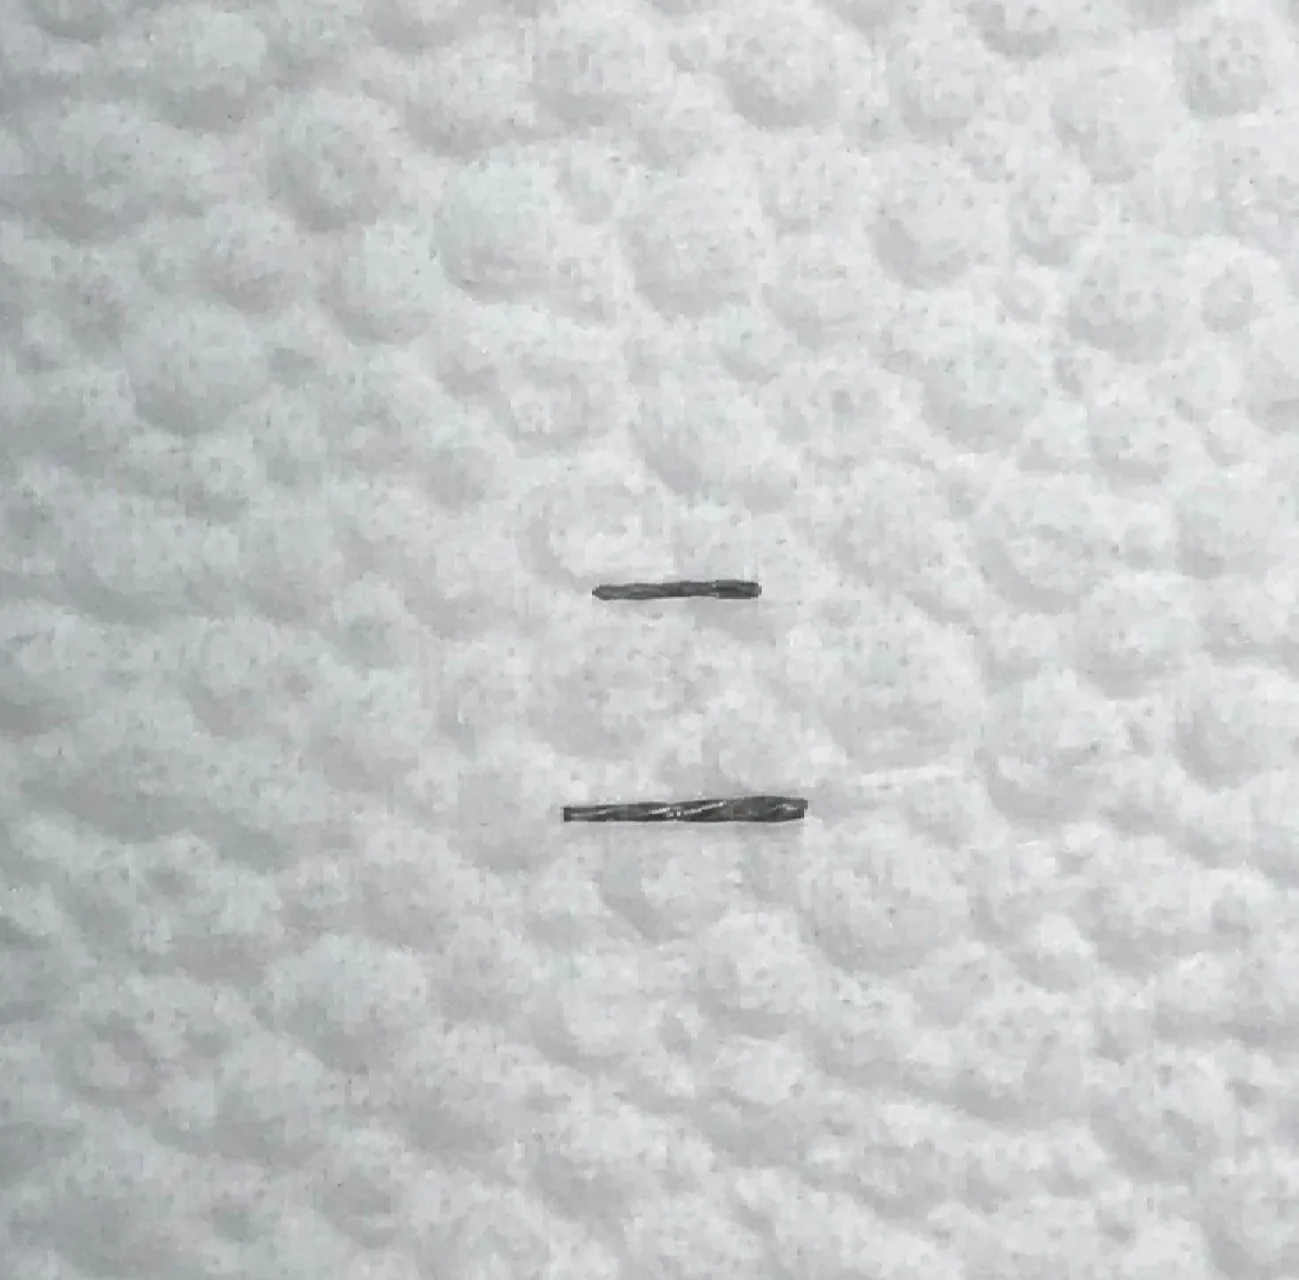

Remoção de Limas

Instrumentos (LIMAS) removidas